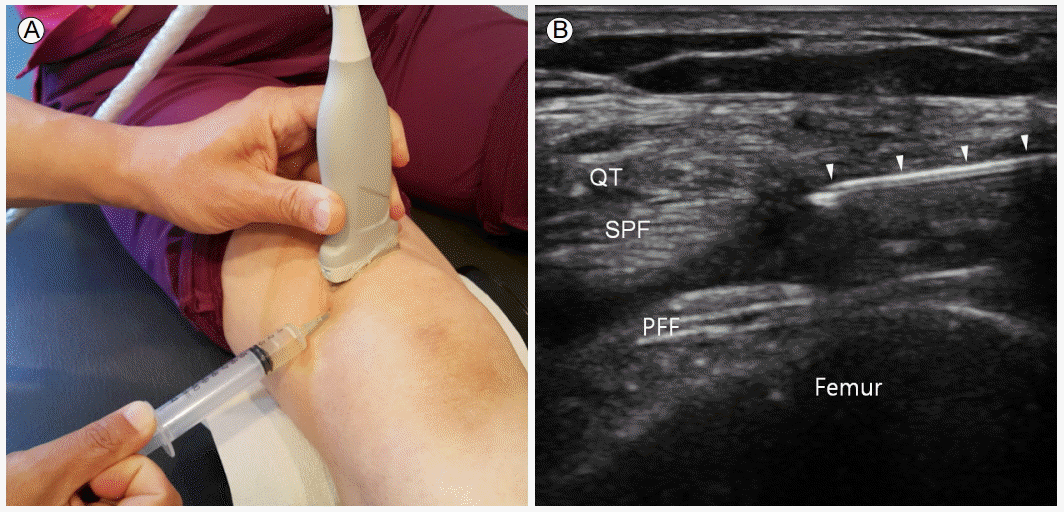

무릎관절내 주사는 일반적으로 영상 유도 없이 높은 정확도로 쉽게 시술되는데, 환자가 비만하거나 삼출액의 양이 매우 적은 경우, 초음파 유도가 도움이 많이 된다[17]. 또한 고분자량의 히알루론산 관절내 주사는 관절외 연부 조직 내로 주사된 경우 심한 통증을 유발할 수 있어 초음파 유도하 주사가 권장되기도 한다[24]. 환자의 자세는 슬와에 필로우를 넣어 무릎을 2-30도 굽힌 상태에서 슬개골의 외측에서 바늘을 진입시킨다(Fig. 9).